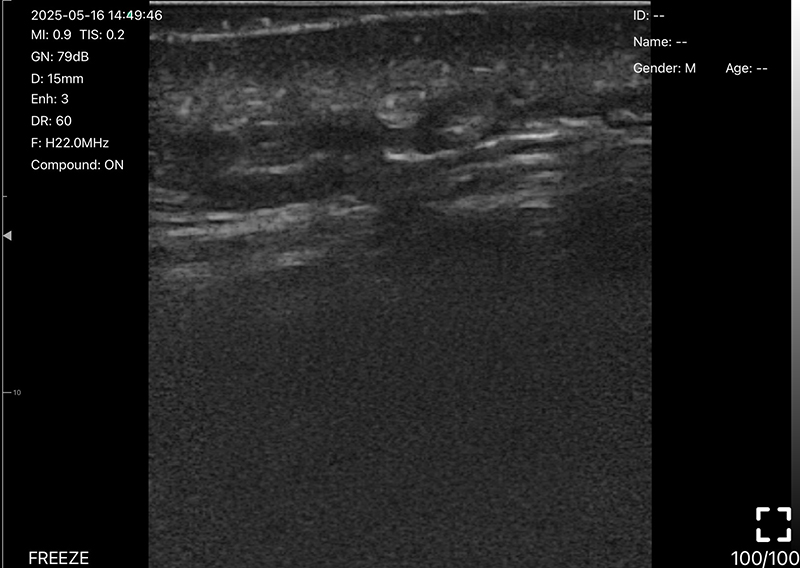

• 探头频率:10/13.2MHz

• 扫描深度:20/30/40/60mm,可调

• B模式

增益:30db-105db

降噪:0-1-2-3-4

动态范围: 40-50-60-70-80-90-100-110

• 图像调节:增益、焦点、

反相脉冲谐波、降噪